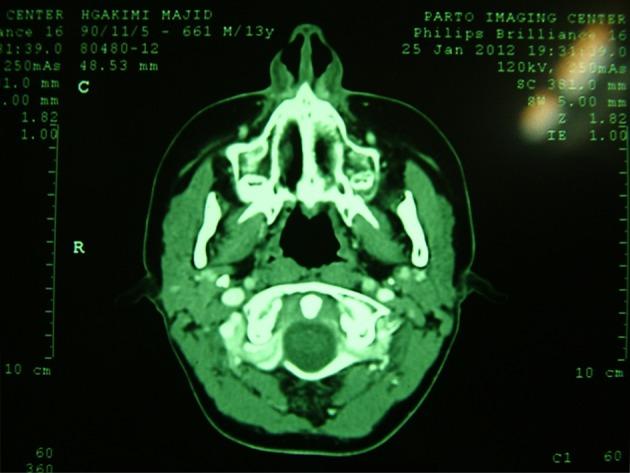

A 15-year-old boy has presented with a mass that located near by the heart in the left side of mediastinum with invasion to anterior mediastinum from two years ago. In biopsy, nasopharyngeal carcinoma, non-keratinizing type, has diagnosed while there was no involvement of nasopharyngeal region. Patient has treated by 70 Gy (2.0 Gy/fraction) radiotherapy plus concomitant chemotherapy with base of docetaxel. But the mass had no regression. Then, the patient has treated with Cisplatin 100 mg/m IV on days 1, 22, and 43 with radiation, then cisplatin 80 mg/m IV on day 1 plus fluorouracil (5-FU) 1000 mg/m/day by continuous IV infusion on days 1 - 4 every 4wk for 3 cycles and after remission interferon beta has added to treatment for 6 months duration as a maintenance therapy. After 1 year follow up; the patient was in complete remission. In the course of therapy, only hypothyroidism has occurred.